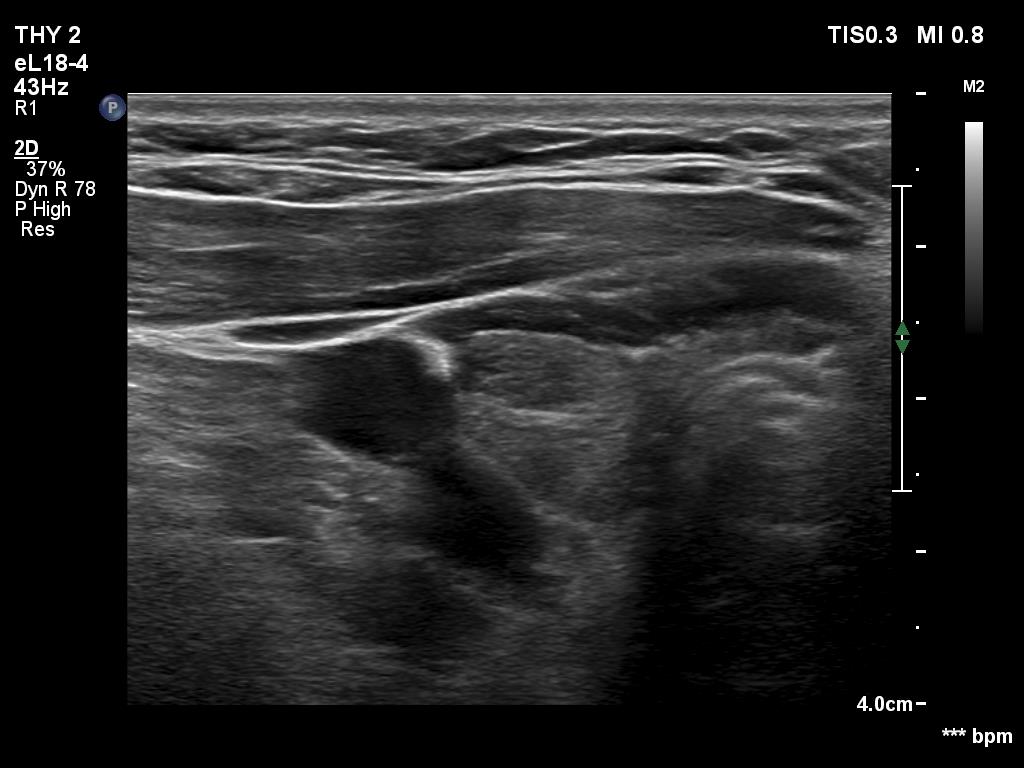

Ultrasonography. The thyroid was hypoechogenic. There was an iso/hyperechoic nodule in both the right and left lobes. The nodule in the left lobe had perinodular vascularity. The dimensions of the nodule in the left lobe were 20x18x31 mm, width, depth, length, respectively. This means that the volume of the nodule has increased almost 8-fold in 10 years.